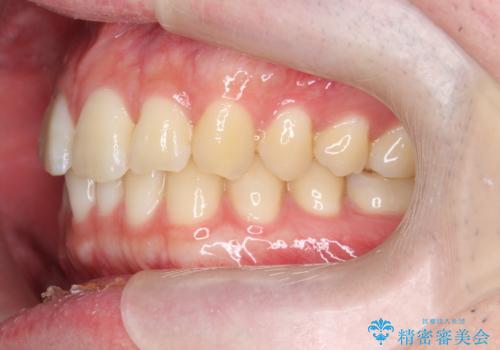

前歯のがたつきをなおしたい マウスピース矯正

- 気になる前歯のがたつきをきれいにしたい。と矯正治療を希望され来院されました。

大きな歯列の乱れはないため、倒れ込んでいる奥歯の傾きの改善、前歯のがたつきを改善する治療を計画します。

見た目が良くなっただけではなく、歯ブラシがしやすくなった!と治療後の歯並びに喜んでいただくことができました。